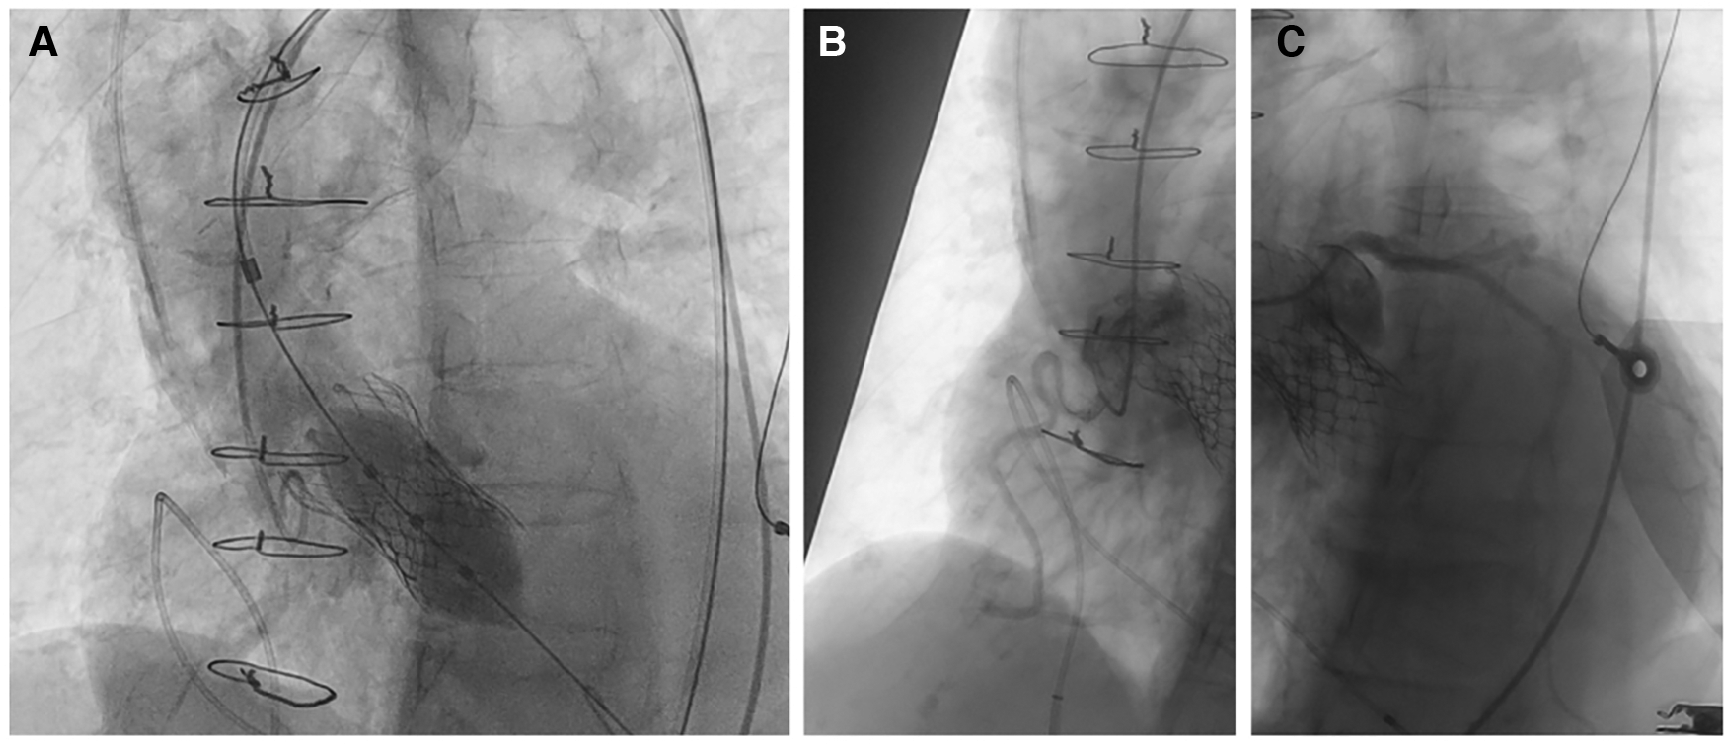

Procedure

Due to the frailty of the patient and the high surgical risk, the cardiac team's consensus was to correct the valve regurgitation with a valve-in-valve TAVI using a Myval 26 mm (Meril, Gujarat, India) valve due to the appropriate size, the radial force achieved by balloon-expandable valves, and the shorter stent frame height of the valve, reducing the neo-skirt. Careful procedural planning was performed in order to assess the anatomical considerations of the slipped Evolut R valve and its relationship to the aortic root. A bifemoral approach was obtained by positioning a 16F transcatheter aortic valve introducer in the right femoral artery and a 6F introducer for a pigtail catheter in the left femoral artery. Due to the severe iliac artery tortuosity, a nitinol hydrophilic guide wire covered with polyurethane Radifocus ™guidewire M (Terumo, Tokyo, Japan) with RJ 4.0 6F support was used. A distal part “S-reshaped” J soft wire-mounted pigtail catheter was used to safely cross the dissected segment (Supplementary Figure S5). The aortic valve was then crossed with a straight tip soft wire using an Amplatz left (AL) 1 catheter (Launcher, Medtronic, Minnesota, USA). The soft wire was exchanged for an extra-stiff 0.0035” Lunderquist wire (Cook Medical, Indiana, USA). We then proceeded with the implantation of a 26 mm Myval valve, which was placed without predilation of the existing Evolut R (Supplementary Figure S6). The Myval valve was positioned at the level of the natural bicuspid aortic valve ring (10/90, outflow/aortic bulbus). Control selective coronary angiography showed good patency of the coronary arteries, and control aortography showed good alignment of the prosthetic valve with no residual aortic regurgitation (Figure 3).

Figure 3

(A) Myval 26 mm positioning no predilation. Good angiographic result with no regurgitation. The position of the valve was at the level of the natural annulus. We avoided overextension of the neo-skirt. (B,C) Unobstructed coronary ostia with good patency.